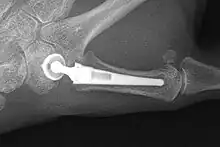

X-ray of trapeziometacarpal joint replacement. Left hand of a 58-year-old woman.

The joint can be replaced with artificial material. An artificial joint is also referred to as a prosthesis. Prostheses are more problematic at the trapeziometacarpal joint compared joints like the knee or the hips.

[27]Prostheses come in many varieties, such as spacers or resurfacing prostheses.

It’s not clear within the current literature that a prosthesis has any advantage over trapeziectomy.[27]

Overall, joint replacements are related to long-term complications such as subluxation, fractures, synovitis (due to the material used) and nerve damaging.[35] In many cases revision surgery is needed to either remove or repair the prosthesis. Also note that usage of a joint replacement is heavy in costs.

The quality of the prostheses is improving and there is reason to believe this will have a positive effect on outcome in the years to follow.[27]